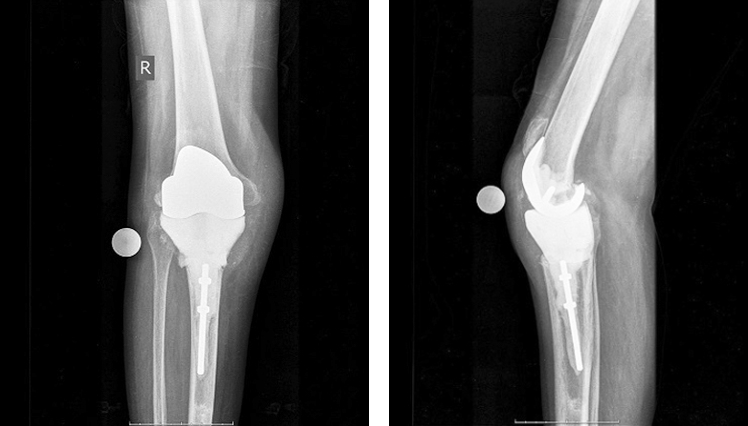

Через 3 года, в 2018 г., вновь стала повышаться температура, отмечалась гиперемия сустава, открылся свищ. С этими жалобами пациентка впервые обратилась в нашу клинику (рис. 1). Пункция сустава с микробиологическим исследованием пунктата выявила наличие золотистого стафилококка, подтвержден рецидив перипротезной инфекции (ППИ) правого коленного сустава. Выполнены санация и установка артикулирующего спейсера. Обширный дефект большеберцовой кости, образовавшийся после удаления связанного эндопротеза, замещен спейсером, изготовленным с использованием 3D технологий.

Рис. 1. Рентгенограммы коленного сустава в прямой и боковой проекциях с установленным связанным имплантатом при поступлении в клинику